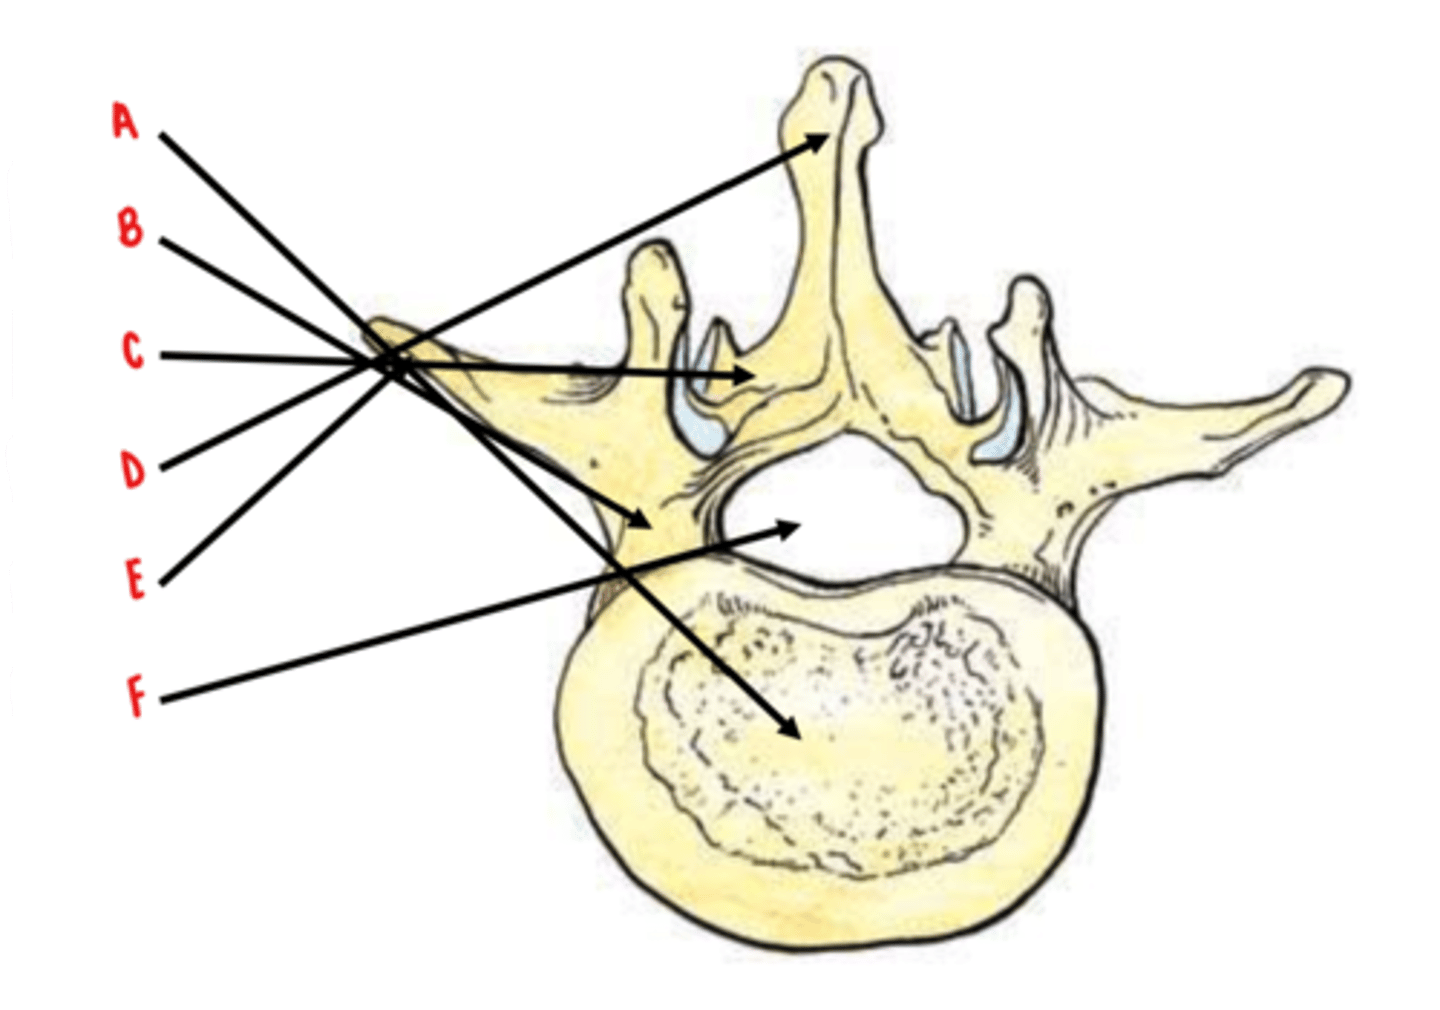

50 Terms

body

Identify A

pedicles

Identify B

laminae

Identify C

spinous process

Identify D

transverse process

Identify E

vertebral foramen

Identify F